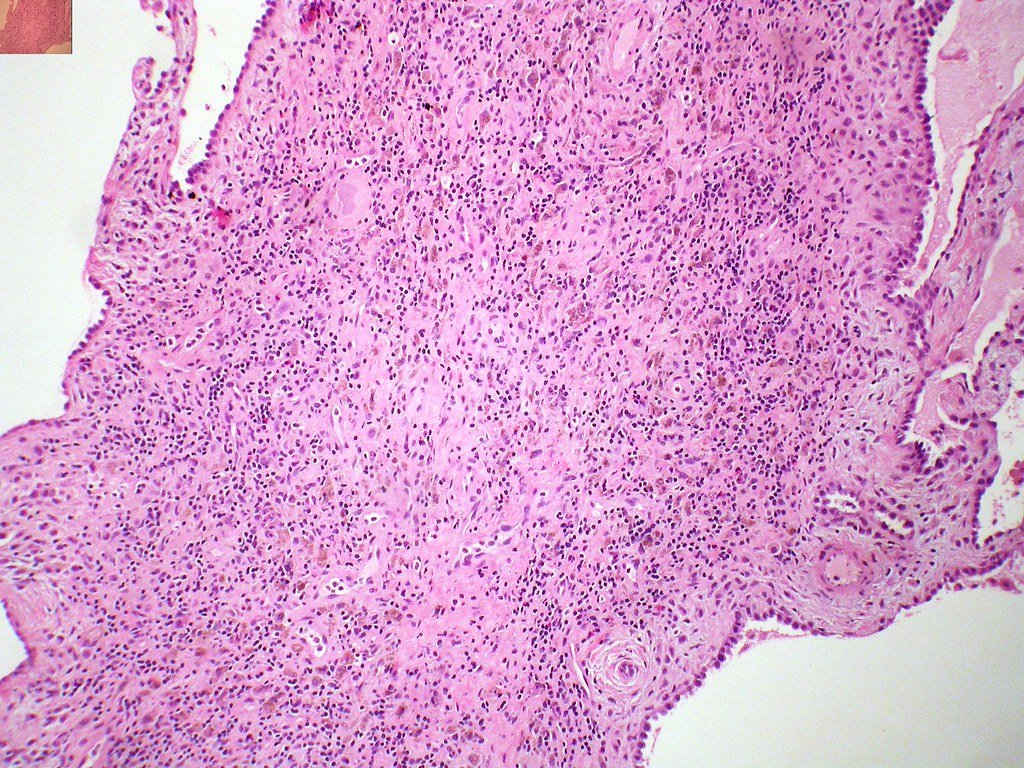

Melanocytes: More Than Skin Deep

Melanocytes, the pigment cells in human skin, are like tiny umbrellas protecting us from harmful radiation. But their job description goes way beyond sun protection. These cells are constantly communicating with surrounding tissues, sending chemical signals that influence everything from wound healing to immune responses. Recent research has shown that melanocytes in different parts of the body behave differently – those in your scalp work differently than those on your arms. What’s truly fascinating is that melanocytes don’t just respond to sunlight; they also react to stress hormones, inflammation, and even the foods we eat. This complex behavior makes them crucial players in overall health, not just appearance.

The medical applications of pigment cell research extend far beyond treating skin conditions. Scientists have discovered that melanocytes share surprising similarities with neurons, the cells in our brain and nervous system. This connection has opened new avenues for treating neurological diseases like Parkinson’s and Alzheimer’s. Researchers are now exploring how the same mechanisms that control pigment production might influence brain function and disease progression. Additionally, studies on pigment cells have led to breakthroughs in understanding autoimmune diseases, where the body mistakenly attacks its own pigment-producing cells. These discoveries are revolutionizing how we approach complex medical conditions that seemed unrelated to skin color.

Melanoma, one of the most aggressive forms of skin cancer, has taught us incredible lessons about how cells become cancerous. But the insights from studying pigment cell cancers have applications far beyond skin cancer treatment. Scientists have found that the same cellular pathways involved in melanoma also play roles in other types of cancer. The ability of pigment cells to migrate and change shape – normally used for development and repair – becomes dangerous when these cells turn cancerous. Understanding these mechanisms has led to new cancer treatments that target specific cellular behaviors rather than just trying to kill cancer cells. This research has contributed to the development of immunotherapy treatments that are now helping patients with various types of cancer.